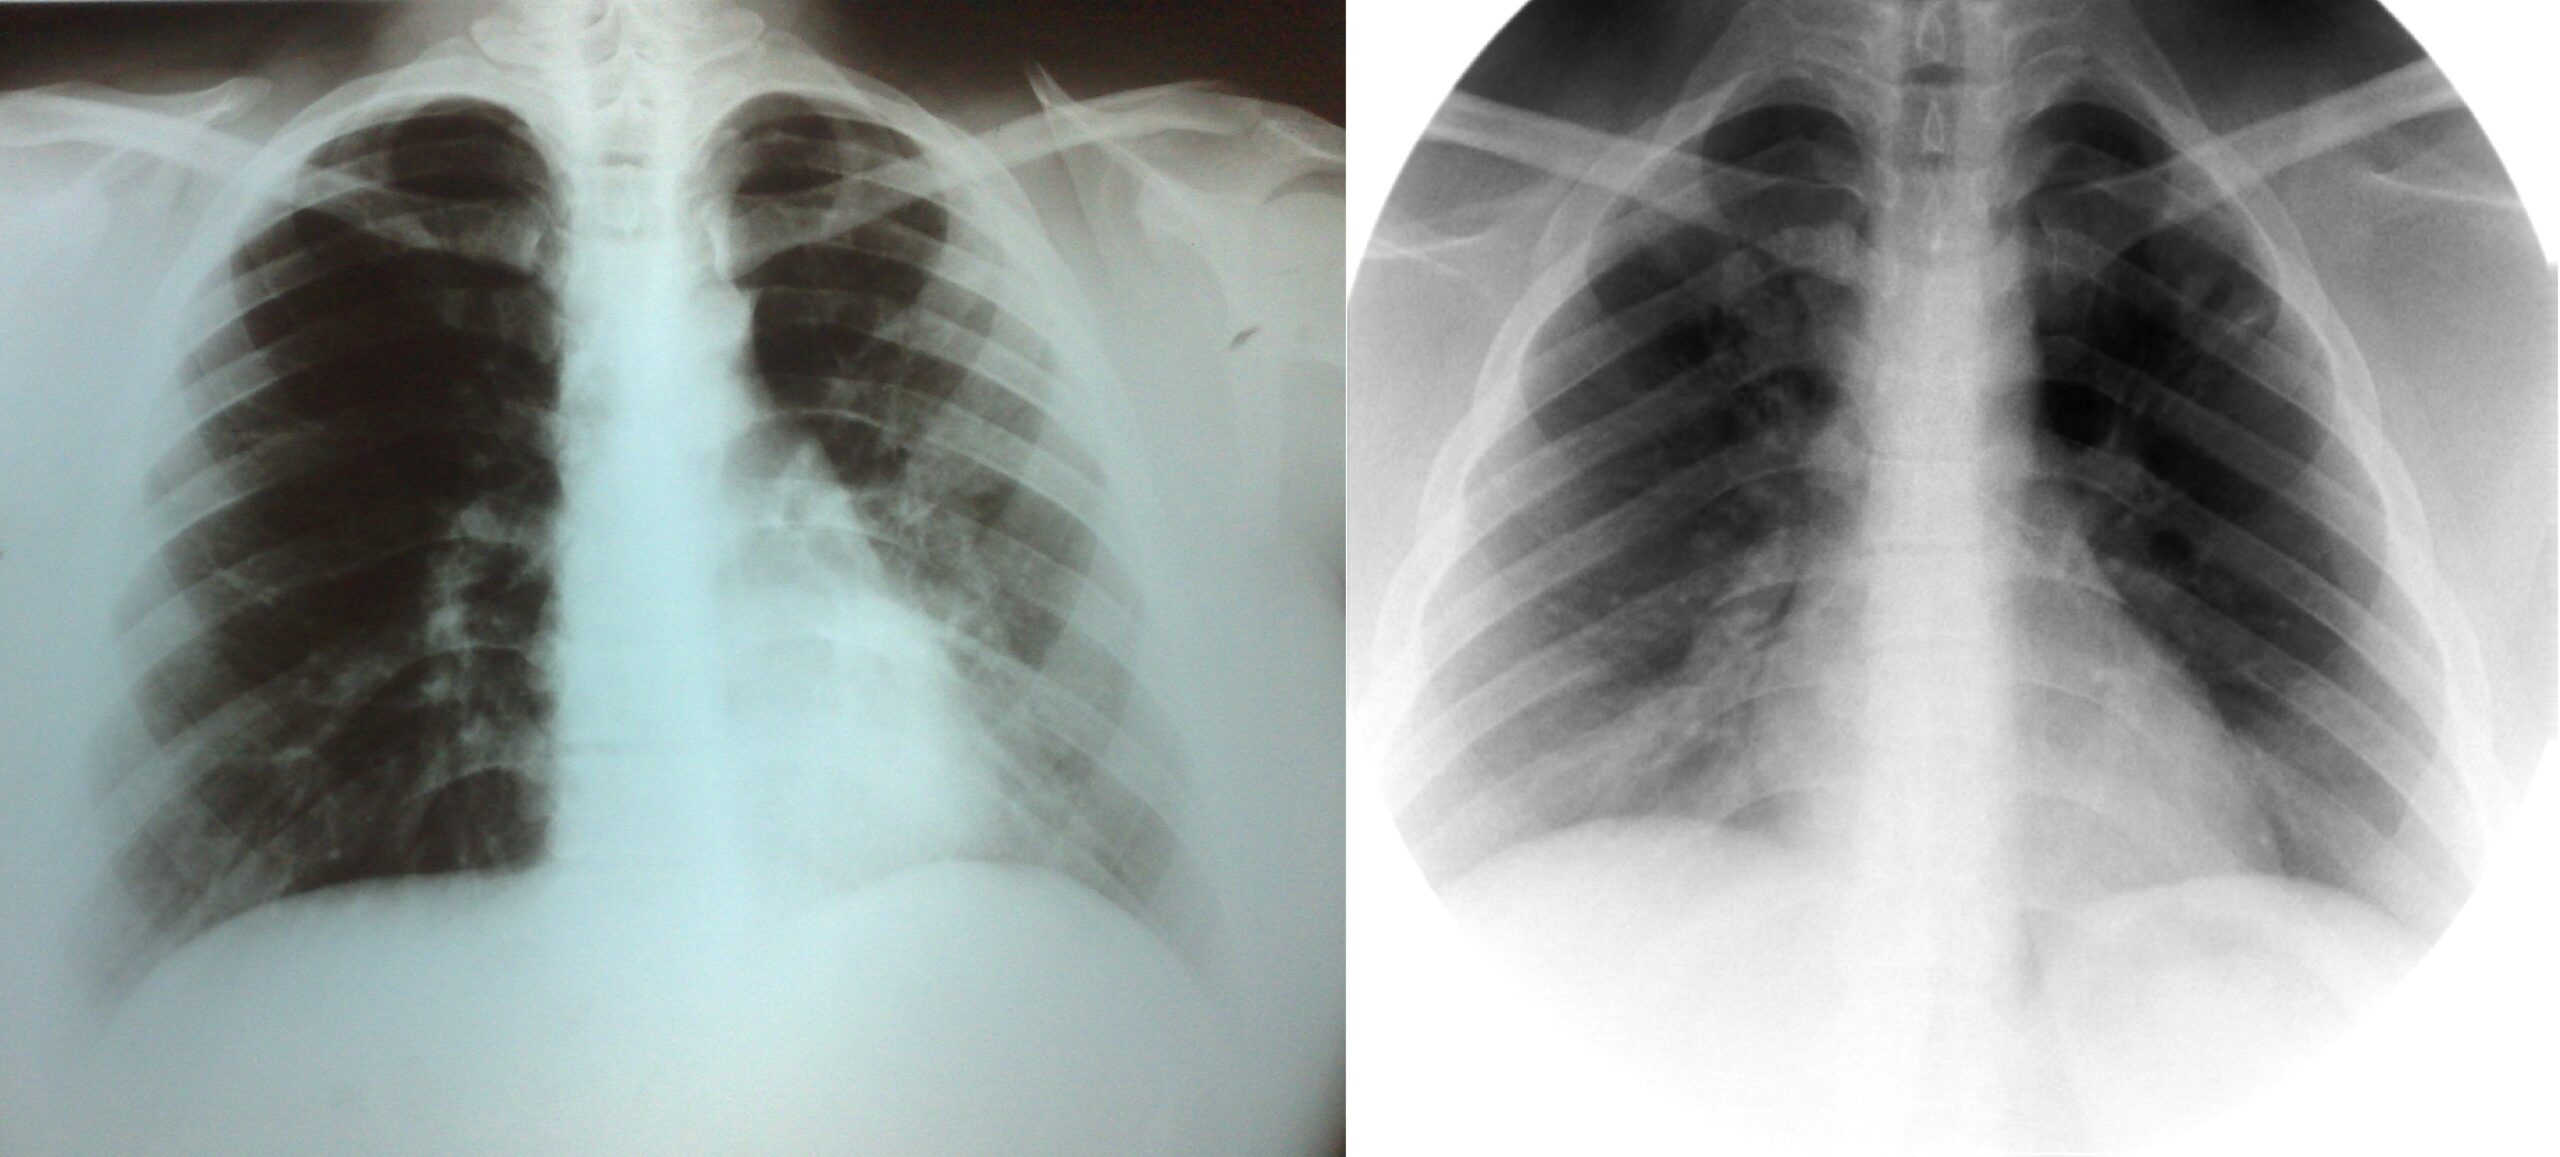

პაციენტი 37 წლის ქალი. 1997 წ-ს გაკეთებული აქვს მარჯვენა ზედა წილის რეზექცია ფილტვის ტუბერკულოზის გამო. წლების განმავლობაში აქვს გამწვავებები, რაც გამოიხატება მაღალი ცხელებით, ხველით, დიდი რაოდენობით სისხლნარევი, მძაფრი სუნის მქონე ნახველის გამოყოფით. რენტგენოლოგიურად...